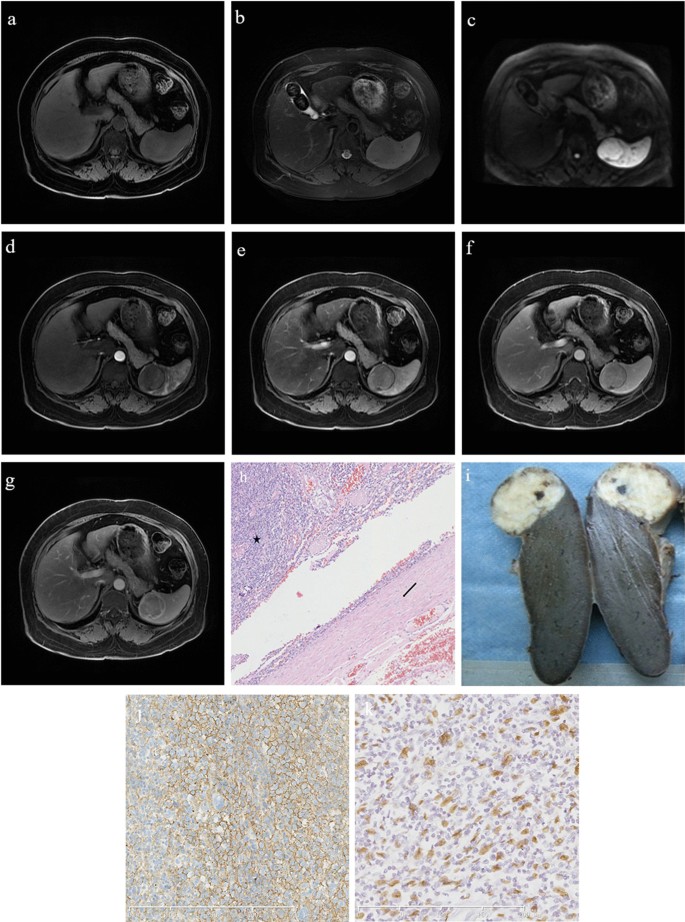

Fig. 5

A 37-year-old male patient with inflammatory pseudotumor-like follicular dendritic cell sarcoma of the spleen. a The mass shows a slight hyperintensity on the T1-weighted image sequence. b On the T2-weighted image sequence, the tumor shows a slightly hypointense signal, and its edge displays a hypointense annular signal representing the pseudocapsule. c The mass shows a slightly hyperintense signal on diffusion-weighted imaging. dg The contrast enhancement of the mass is mild in each phase, and the pseudocapsule shows delayed enhancement. h On histopathological examination, the tumor (black star) is surrounded by dense fibrous tissue (black arrow; hematoxylin and eosin, ×100). i Macroscopic examination showing a grayish-white tumor with uniform texture and clear boundaries. j CD21 is diffusely positive. k Epstein–Barr virus is detected in almost all of the tumor cells with positive dark staining of their nuclei

All liver tumors demonstrated slightly hypointense signals on T1-weighted images (Fig. 4a) and slightly hyperintense signals on T2-weighted images, with unclear edges and a “halo sign” present in 2 of 3 cases (67%) (Fig. 4b). The diffusion-weighted imaging sequence showed slightly high or high signal intensities (Fig. 4c). The liver lesions demonstrated substantial enhancements from the center to the periphery in the arterial phase (Fig. 4d). The enhancement amplitude of the lesions in the portal, venous, and delayed phases tended to be homogeneous and decreased in varying degrees, and annular enhancements could be seen (Fig. 4e, f). Seven of the nine cases with splenic lesions showed slight hyperintensities on T1-weighted images (Fig. 5a), slight hypointensities on T2-weighted images (Fig. 5b), slightly high or high signal intensities on diffusion-weighted images (Fig. 5c); and a hypointense ring on T2-weighted images could be seen at the lesion’s margin (Fig. 5b). There was mild-to-moderate heterogeneous enhancement; after enhancement, the amplitude was always lower than that of the normal splenic tissue, and annular enhancement could also be seen in the delayed phase (Fig. 5d–g). Significant differences between liver and spleen IPT-like FDCSs were found when comparing T1 and T2 signal intensities, enhancement patterns, and the presence of “halo signs” (Table 4).

Pathology results

Immunophenotypically, the tumor cells were strongly positive for CD21 (Fig. 5j) and CD35 in 13 cases and for CD23 in three cases. Clusterin staining showed strong positive findings in the cytoplasm in three cases. Some tumor cells were positive for CD68, smooth muscle actin, vimentin and epidermal growth factor receptor. The Ki-67 index was 5–30%. All cases were positive for EBER by in situ hybridization analysis (Fig. 5k).